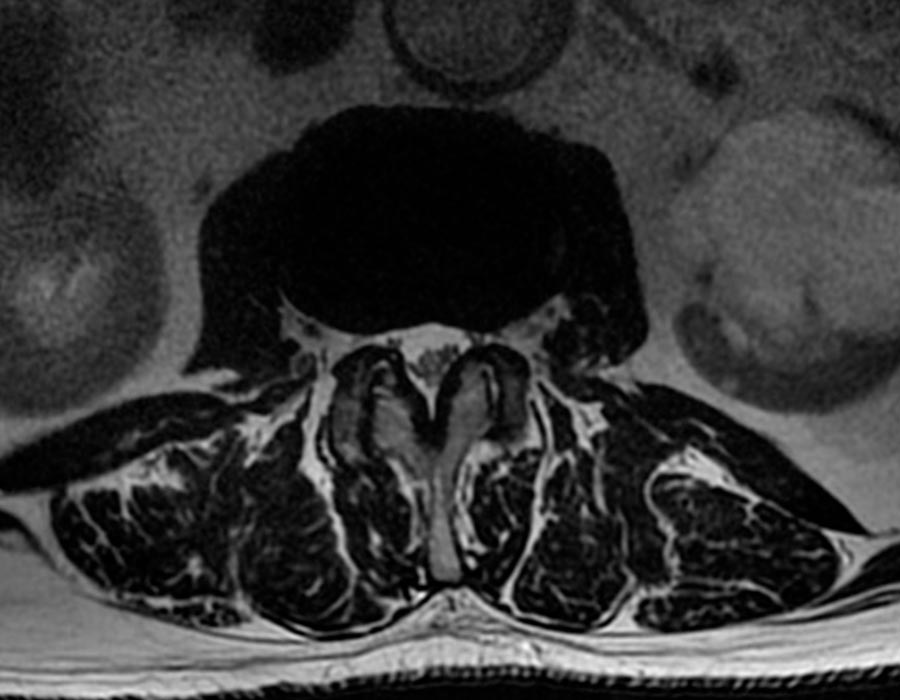

Se procede a realizar una hemilaminectomía hasta comprobar la adecuada liberación de las estructuras neurológicas que recorren el canal vertebral.

Una vez comprobado que el canal tiene el espacio suficiente y que todas las partes atrofiadas han sido retiradas, se procede a retirar parte del TIP de la faceta ascendente para evitar la compresión de las estructuras neurológicas de nuevo.

Vision transversal columna vertebral operacion